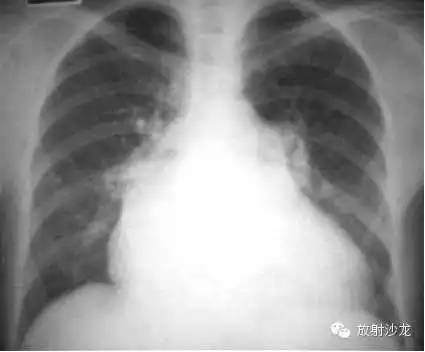

冠心病 心肌梗塞 室壁瘤形成